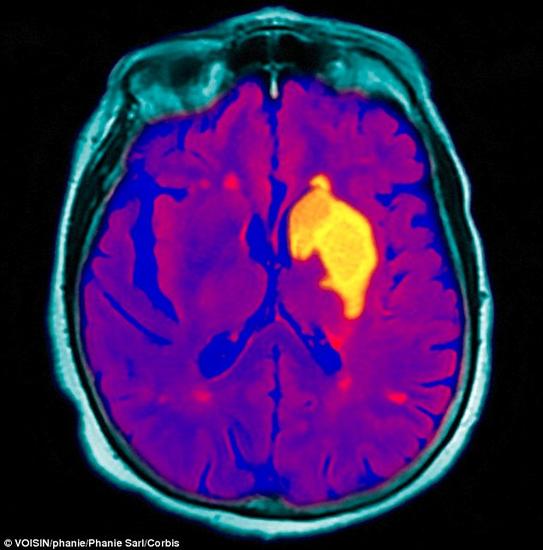

4. 脑血管疾病

通常,脑血管疾病表现为中风,是由于血管破裂或血栓阻塞导致脑部供血中断而引发的一种疾病。脑部供血中断会切断氧和营养物的供应,导致大脑组织损伤。据世界卫生组织估计,2012年大约有1750万人死于心血管疾病,如心脏病。不过,80%的过早心脏病发作和中风都是可以预防的。常见的心血管疾病预防方法有健康的饮食、定期的体育活动,以及戒烟,定期检查并控制引发心脏病和中风的风险因素,例如高血压、高胆固醇和高血糖或糖尿病,也非常关键。中风的常见症状有:面瘫、四肢麻木、半身不遂、口舌歪斜,舌强语蹇或不语、偏身麻木、行动失调、眩晕头痛或失去意识。中风的后果依大脑受损的部位和程度的不同而不同,严重情况下会导致突然死亡。